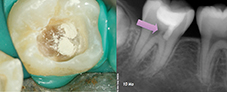

Photo 6 : Cas n° 2 : Radiographie à 12 mois.

Photo 7 : Cas n° 3 : État initial.

Photo 8 : Cas n° 3. Coiffage pulpaire et résultat à 10 mois.